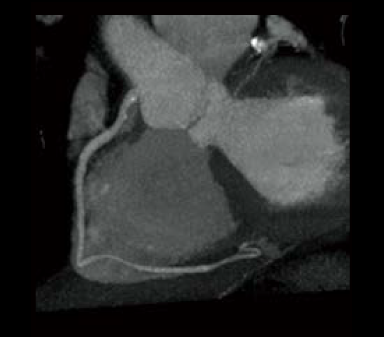

Cardio StillShot: ON